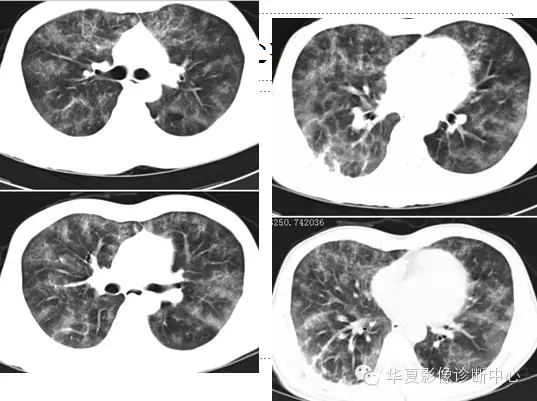

两肺野弥漫性分布的斑点及斑片状阴影,呈“暴风雪”样,病变以两中下肺野为多,部分小叶间隔增厚,心脏大小正常。纵隔窗显示右侧胸腔后下部少量积液。。

诊断:肺脂肪栓塞综合征。